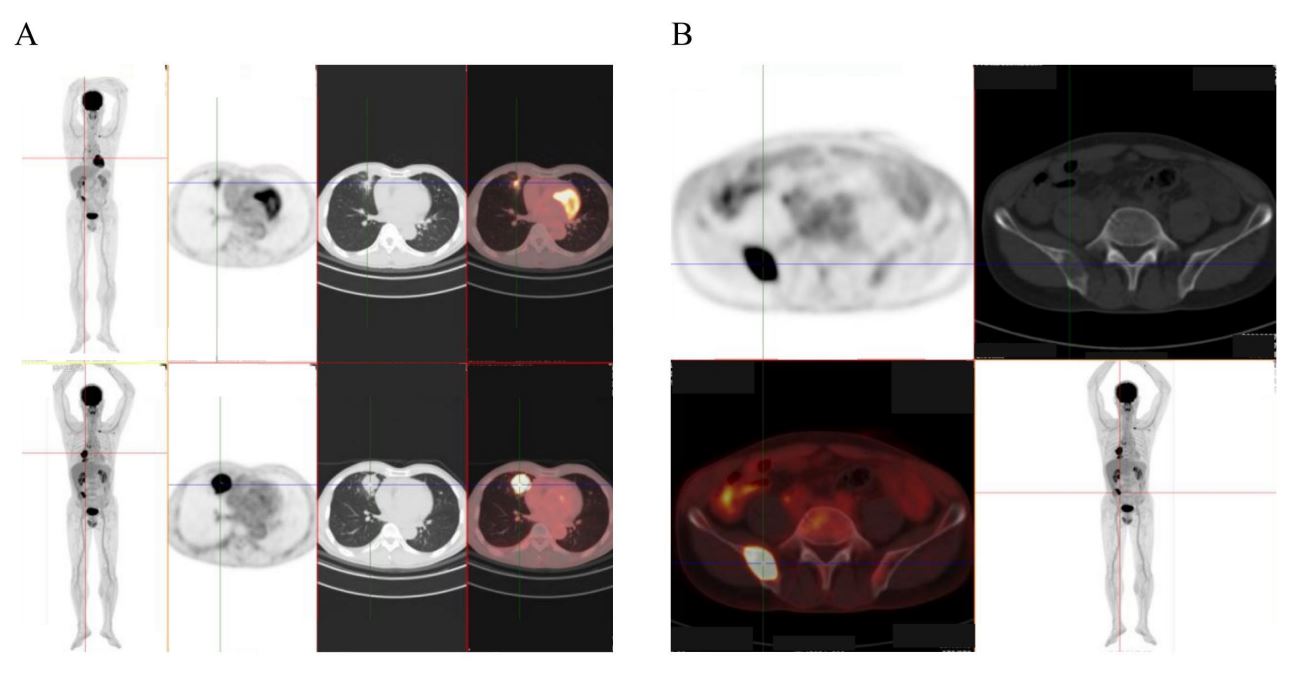

Last year, my father, aged 54, experienced a cough with hemoptysis lasting over a month. An initial CT scan suggested a diagnosis of lung cancer. Unfortunately, following a PET/CT (FDG-whole body imaging), not only was there a tumor approximately 4.2×4.2 cm in size identified in the right middle lobe of the lung, but also evidence of bone metastasis within the ilium, as shown in Figure 1. Ultimately, histological examination confirmed the diagnosis of Non-Small Cell Lung Cancer (NSCLC). Based on our analysis, the current situation of the father is living with lung cancer with a solitary bone metastasis. According to the 2022 CSCO (Chinese Society of Clinical Oncology) guidelines in China, for patients with a Performance Status (PS) scoring of 0-1 and lung lesions classified as N2 or T4, the recommendation includes sequential or concurrent chemo radiotherapy plus radiation therapy for bone metastatic lesions, combined with bisphosphonate or denosumab treatment, in addition to systemic chemotherapy (Category 2B evidence). Studies have shown that patients undergoing this treatment approach can benefit, with a median survival time of 13.5-14 months and overall survival rates at 1, 2, and 3 years of 58.1%, 24.8%, and 15.8%, respectively [5-7]. After medical decision-making discussions, my father underwent treatment with paclitaxel and carboplatin chemotherapy in conjunction with toripalimab immunotherapy, administered every 20 days. The treatment course proceeded smoothly with no significant discomfort. Following three treatment cycles, PET/CT (FDG-whole body imaging) revealed a marked reduction in the lesions, as illustrated in Figure 1. However, it is disheartening that my father experienced significant hair loss, which inevitably raises concerns regarding the toxic side effects of chemotherapy.

Figure 1: PET/CT images. (A) Changes in tumor size before and after treatment. (B) PET/CT images of metastatic lesions.